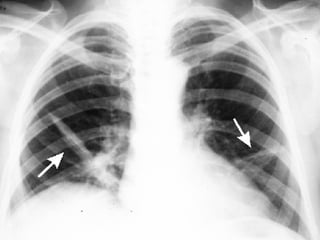

Bilateral pleural effusions

• #12 With heart failure edema builds up in lungs and edema along fissures allows them to be seen more easily on chest x-ray